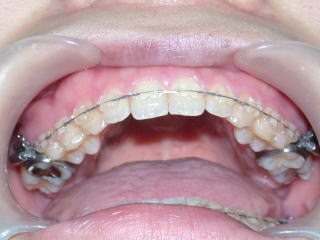

術後を予測するセットアップモデル。